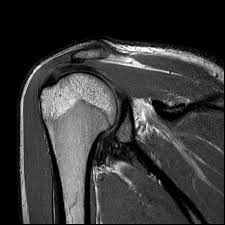

Musculoskeletal MRI is a non-invasive imaging technology that provides detailed images of bones, joints, and soft tissues. Unlike traditional X-rays, which only highlight bones, MRI gives a comprehensive view of the musculoskeletal system. It can detect abnormalities in muscles, ligaments, cartilage, and tendons, offering a clear picture of what might be causing pain or discomfort.

Raj’s experience with the Musculoskeletal MRI was equally transformative. His scan revealed inflammation in the rotator cuff, a common issue among those who engage in repetitive arm movements. With this knowledge, Raj’s doctors tailored a rehabilitation program that allowed him to manage his condition effectively. Within months, he was back to painting, his spirit and creativity reignited.